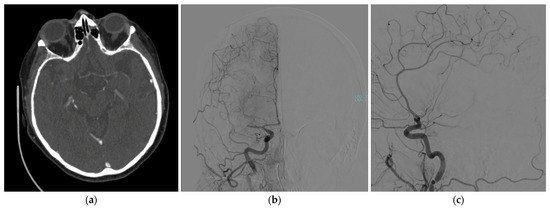

2. Case Presentation